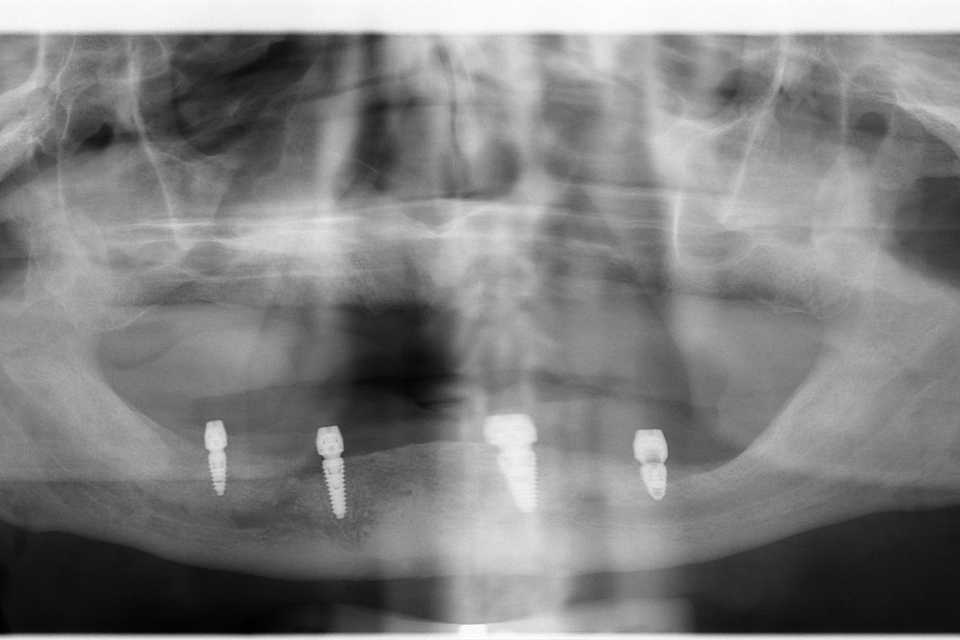

Implanturi mandibulă și lucrare înșurabilă ceramică

Cazul 66: Implant dentar MegaGen AnyRidge

Pacient în vârstă de 77 de ani, purtător de proteză mobilă de peste 20 de ani, nemulțumit de faptul că nu mai poate purta proteza din cauza rezorbției osoase la nivelul mandibulei, se hotărăște pentru o reabilitare protetică fixă cu ajutorul implanturilor dentare și a unei lucrări înșurubabile din ceramică pe suport de titan.